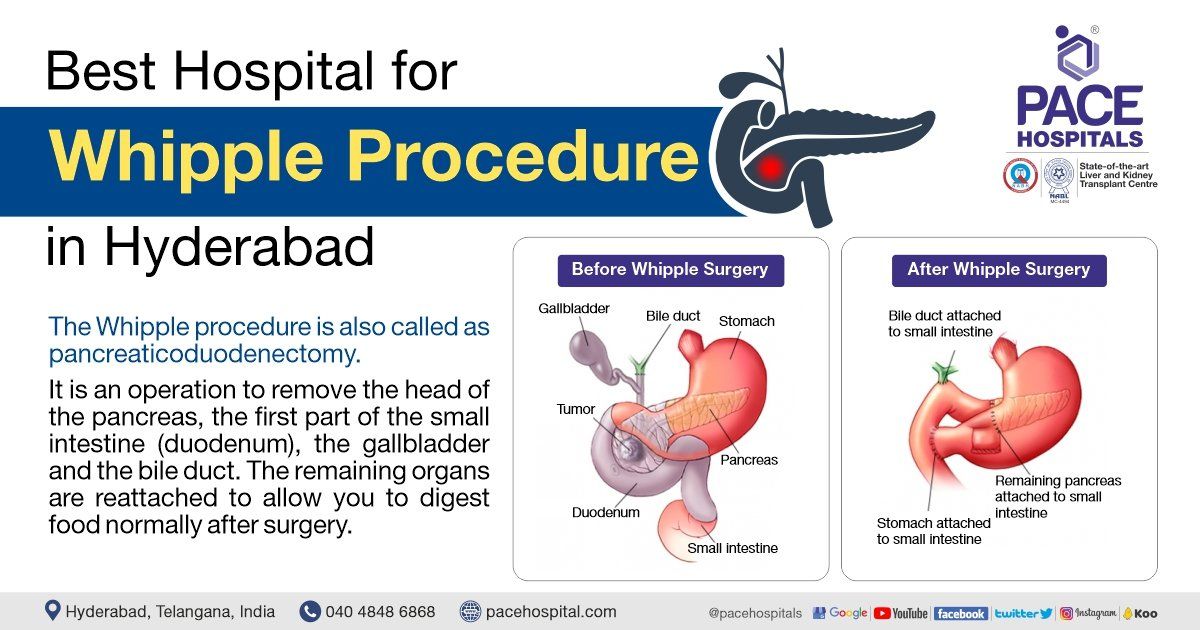

Whipple Procedure Steps Complications Purpose And More 40 OFF

https://lirp.cdn-website.com/69c0b277/dms3rep/multi/opt/Best+Hospital+for+Whipple+Procedure+in+Hyderabad-1920w.jpg

Whipple Procedure Anatomy

Whipple Procedure Diagram

Whipple Procedure Johns Hopkins Medicine

Whipple Procedure Diagram